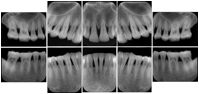

Intra-oral radiography typically involves acquisition of multiple images of various parts of the dentition. Many digital radiographic systems offer customized templates that are used for displaying the images in a study on the screen. These templates may also be referred to as mounts or view sets. The Structured Display Object represents a standard method of encoding and exchanging the layout and intended display of Structured Displays. A structured display object created in this manner could be stored with a study and exchanged with images to allow for complete reproduction of the original exam.

2. A patient requests cosmetic surgery to enhance their facial appearance. The case requires consultation between an orthodontist in New York and an oral surgeon in California. The cephalometric series of 2D projections constructed from a volumetric CT data set that is used for the discussion is arranged by a Structured Display for transfer between the two practitioners.

Cephalometric Series Structured Display

Figure OO-2. Cephalometric Series Structured Display